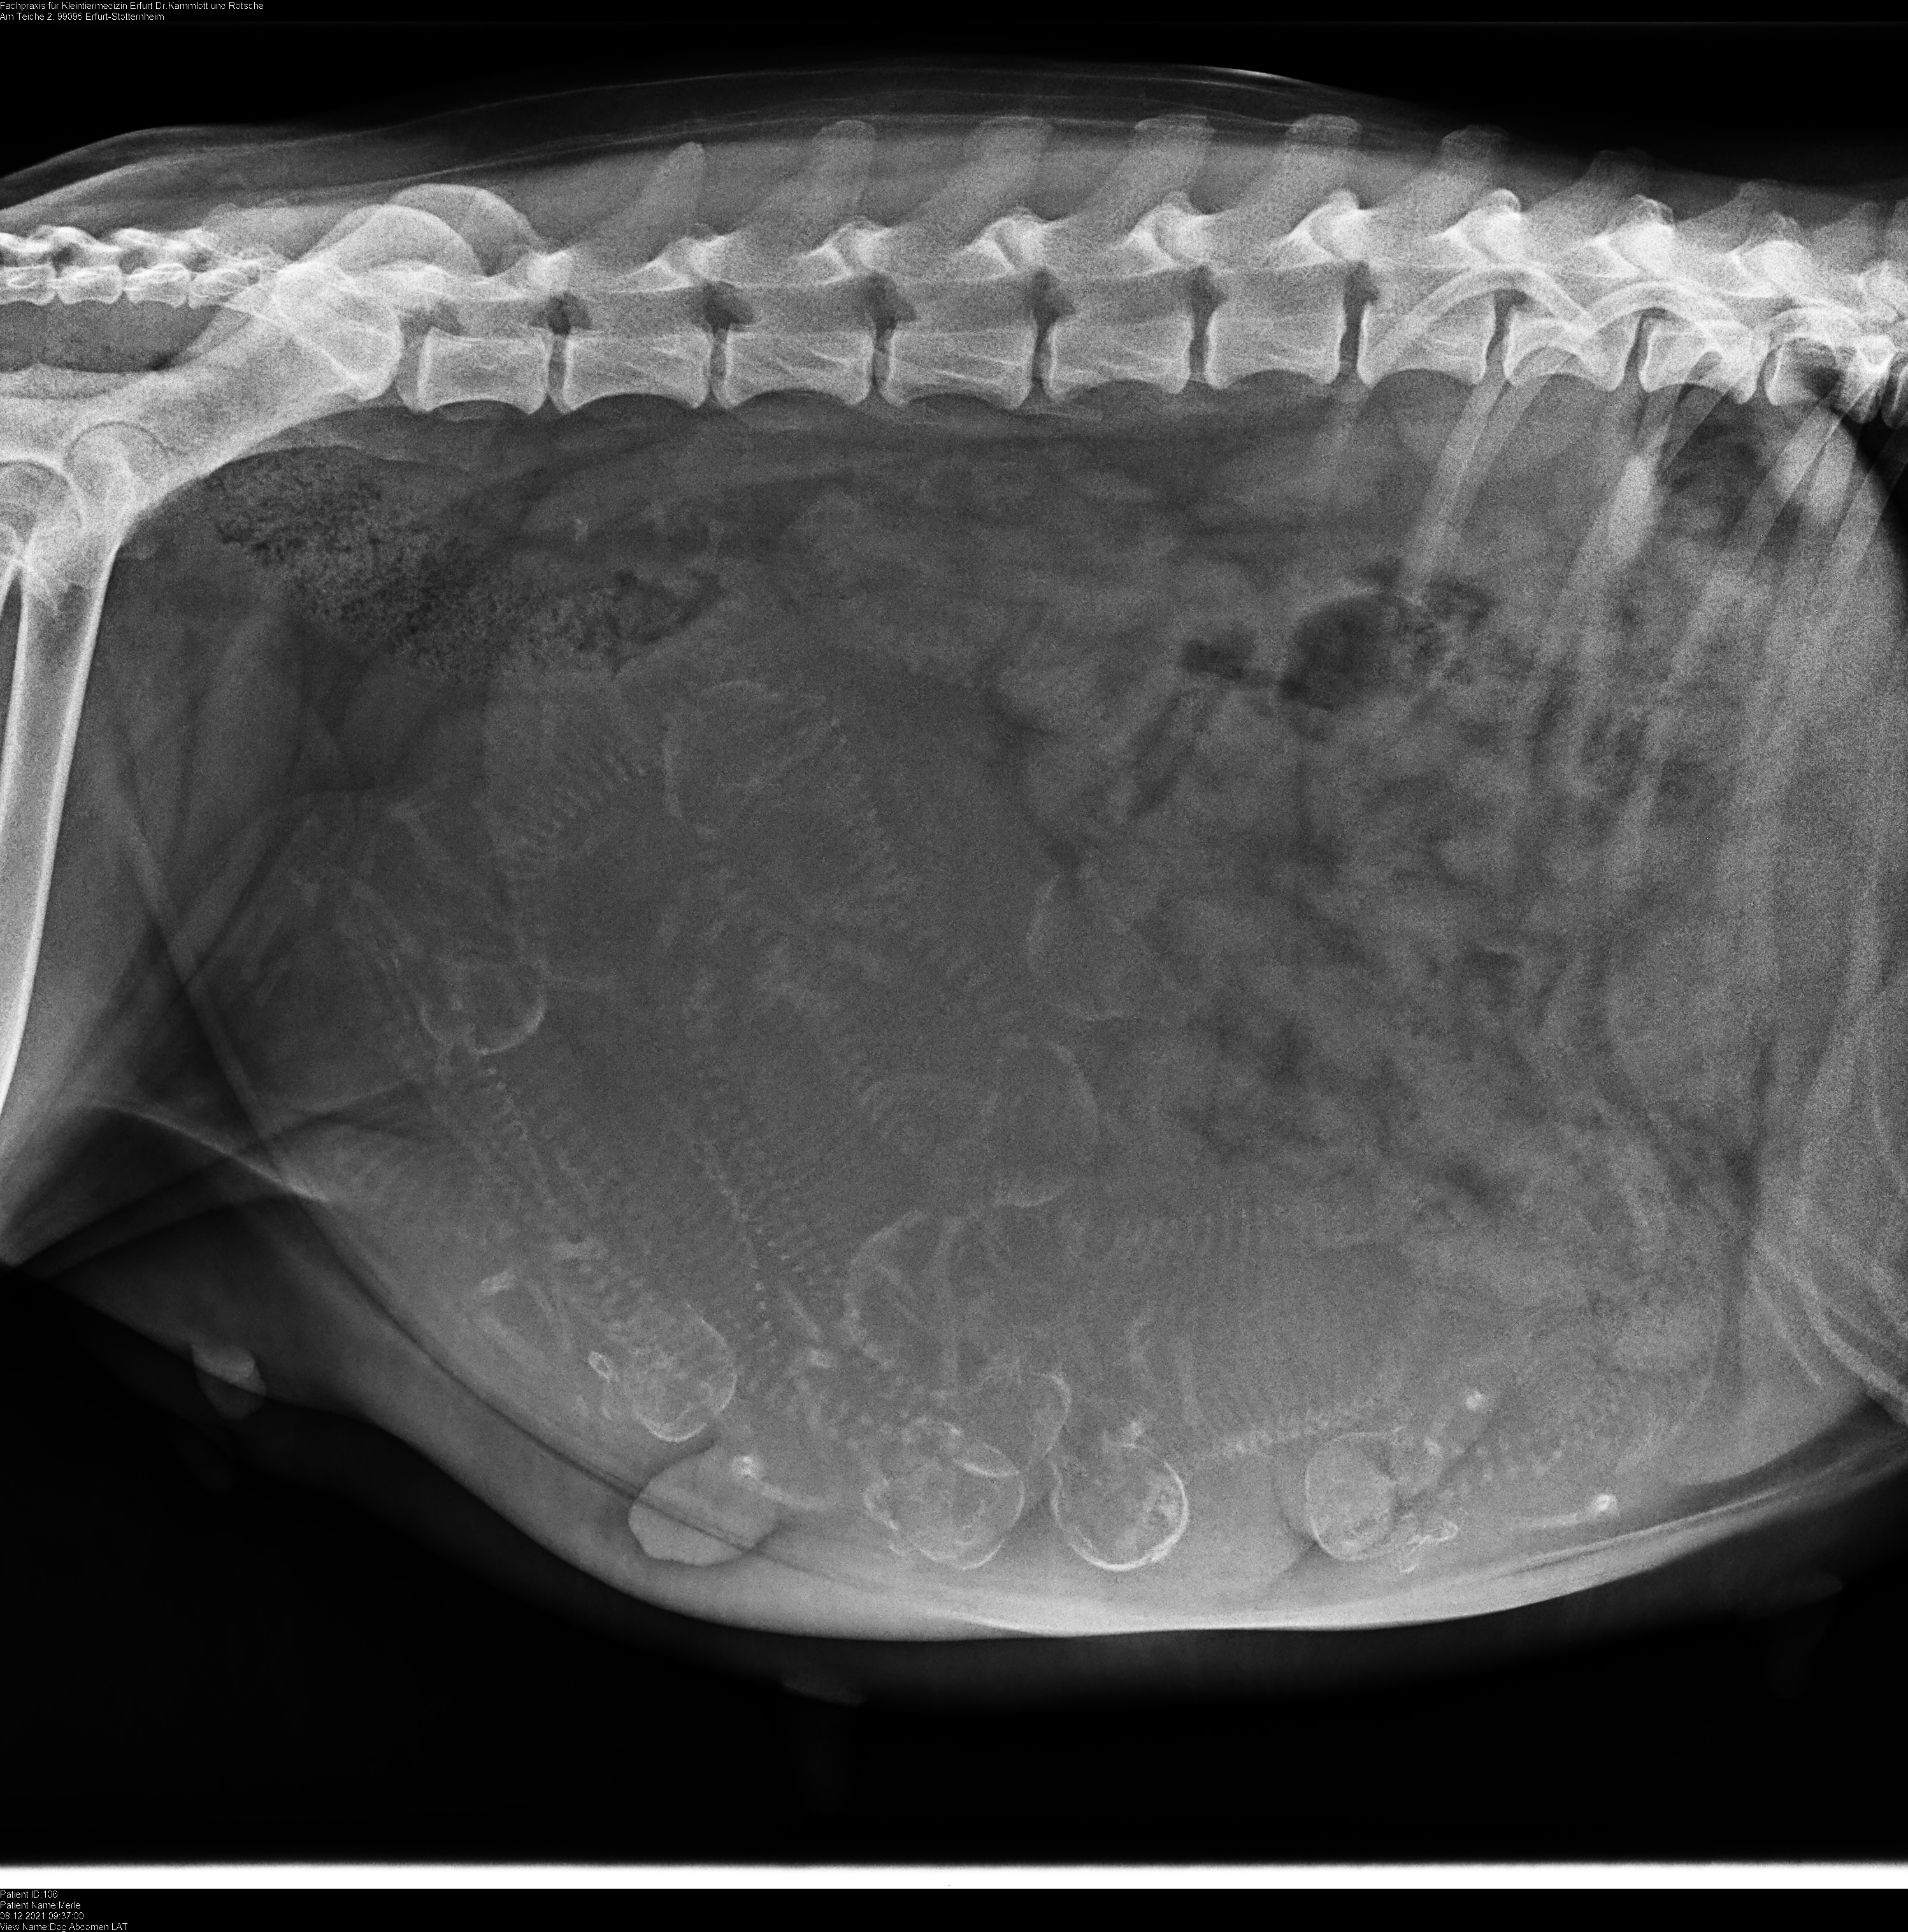

Die Welpen nach der Geburt, 19.12.2021